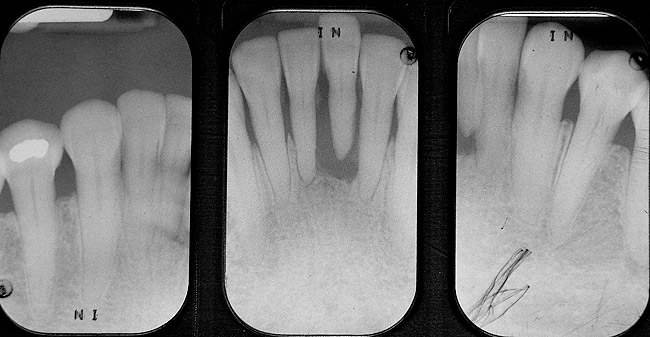

In vitro studies have demonstrated that the use of unidirectional glass-fiber reinforcement in the connector areas of FPDs contributes to significant composite reinforcement.29,36-38,66-68 Similar findings have been reported with a leno-weave UHMWPE and triaxial weave UHMWPE fiber.20,33,36 Fiber-reinforcing materials used by a dental laboratory are either resin pre-impregnated glass fibers, pre-polymerized composite resin surrounding glass fibers, biaxial braid UHMWPE, leno-weave UHMWPE, or a triaxial weave UHMWPE (Table 3). Typically, the preparation designs for the abutment teeth are inlay or onlay preparations (Figure 6A, Figure 6B, Figure 6C, Figure 6D). They are highly successful and can provide the patient with clinical service for more than 5 to 10 years.69 These restorations must be cemented using an adhesive resin technique with resin cements. Both etch-and-rinse adhesives with a self-cure or dual-cure composite resin cement or with a self-adhesive resin cement are indicated for cementing these restorations (Figure 7).36-38,70 Also, fiber-reinforcing materials are being used by dental laboratories in the fabrication of provisional restorations to reinforce and strengthen acrylic and composite-resin provisional materials.15,40,71